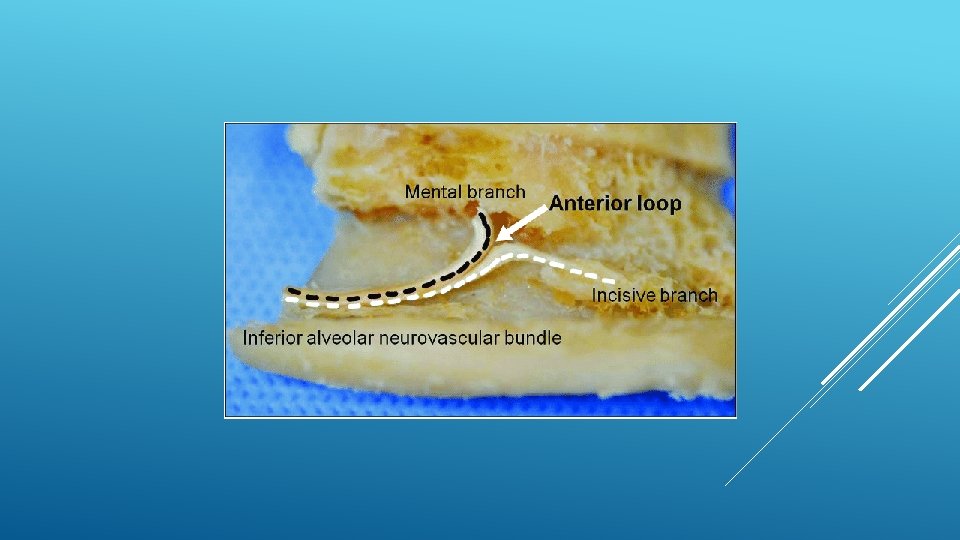

LOCATION AND DIMENSIONS OF THE MENTAL FORAMEN: A RADIOGRAPHIC ANALYSIS BY USING CONE-BEAM COMPUTED TOMOGRAPHY The majority of MF (56%) were located apically between the 2 premolars, and another 35. 7% of MF were positioned below the second premolar. On average, the MF was localized 5. 0 mm from the closest root of the adjacent tooth (range, 0. 3 -9. 8 mm). The mean size of the MF showed a height of 3. 0 mm and a length of 3. 2 mm; however, individual cases showed large differences in height (1. 8 -5. 1 mm) and in length (1. 8 -5. 5 mm). All mental canals exiting the MF demonstrated an upward course in the coronal plane, with 70. 1% of the mental canal presenting an anterior loop (AL) in the axial view. The mean extension of AL in cases with an AL was 2. 3 mm.

THE MENTAL FORAMEN OR "THE CROSSROADS OF THE MANDIBLE. " AN ANATOMIC AND CLINICAL OBSERVATION] [ARTICLE IN FRENCH, GERMAN] THOMAS VON ARX 1 This paper presents a clinical and anatomical review of the mental foramen (MF) based on recent publications (since 1990). Usually, the MF is located below the 2 nd premolar or between the two premolars, but it may also be positioned below the 1 st premolar or below the mesial root of the 1 st molar. At the level of the MF, lingual canals may join the mandibular canal (hence the term "crossroads"). Accessory MF are frequently described in the literature with large ethnic variations in incidence. The emergence pattern of the mental canal usually has an upward and posterior direction. The presence and extent of an "anterior loop" of the mental canal may be overestimated with panoramic radiography. Limited cone-beam computed tomography currently appears to be the most precise radiographic technique for assessment of the "anterior loop". The mental nerve exiting the MF usually has three to four branches for innervation of the soft tissues of the chin, lower lip, facial gingiva and mucosa in the anterior mandible. The clinician is advised to observe a safety distance when performing incisions and osteotomies in the vicinity of the MF.

ANATOMICAL RELATIONSHIP BETWEEN MENTAL FORAMEN, MANDIBULAR TEETH AND RISK OF NERVE INJURY WITH ENDODONTIC TREATMENT he root apex of the mandibular second premolar (70 %), followed by the first premolar (18 %) and then the first molar (12 %), was the closest to the MF. Ninetysix percent of root apices evaluated were >3 mm from the MF. An AL was present in 88 % of the cases. Conclusions: With regards to endodontic treatment, the risk of nerve injury in the vicinity of the MF would appear to be low. However, the high incidence of the AL highlights the need for clinicians to be aware and careful of this important anatomical feature.